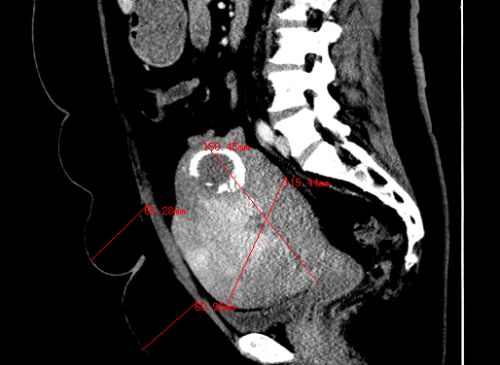

ct显示:子宫内多发肿瘤,子宫增大至16.0×15.0×11.5cm,皮下脂肪层厚达6cm。